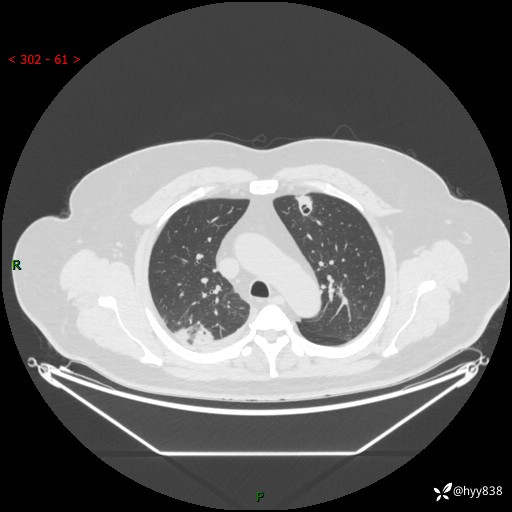

性别:男

年龄:48岁

简要病史:发热来诊(门诊病人)

胸部CT平扫